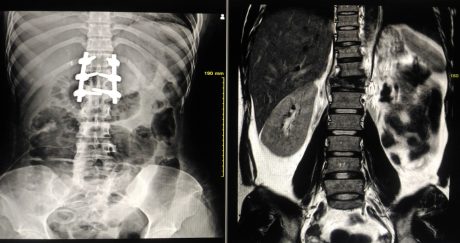

PB’s condition deteriorated to the point that he had to move in with his mother for support. Eventually, he collapsed at his mother’s home and was admitted to hospital via ambulance. Initially, an abdominal infection was suspected, but a CT scan revealed signs of a spinal infection, and PB underwent an MRI scan the next day to confirm this. He was then prescribed IV antibiotics to treat the infection. Shortly after this, it was found that PB was developing weakness in his legs as a consequence of spinal cord compression and was transferred for urgent spinal surgery at another hospital. The operation decompressed his spinal cord, removed the infection that had formed an abscess and added instrumentation to stabilise his spine.

Following surgery, PB was on bed rest for six weeks and on antibiotics for three months. He had to undergo another surgery two months later to stabilise screws that had been displaced from the first operation.